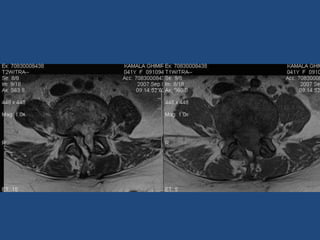

Tb/ Mg – L5 25/M

Tb/ Mg – L5

Tb/ Mg L5